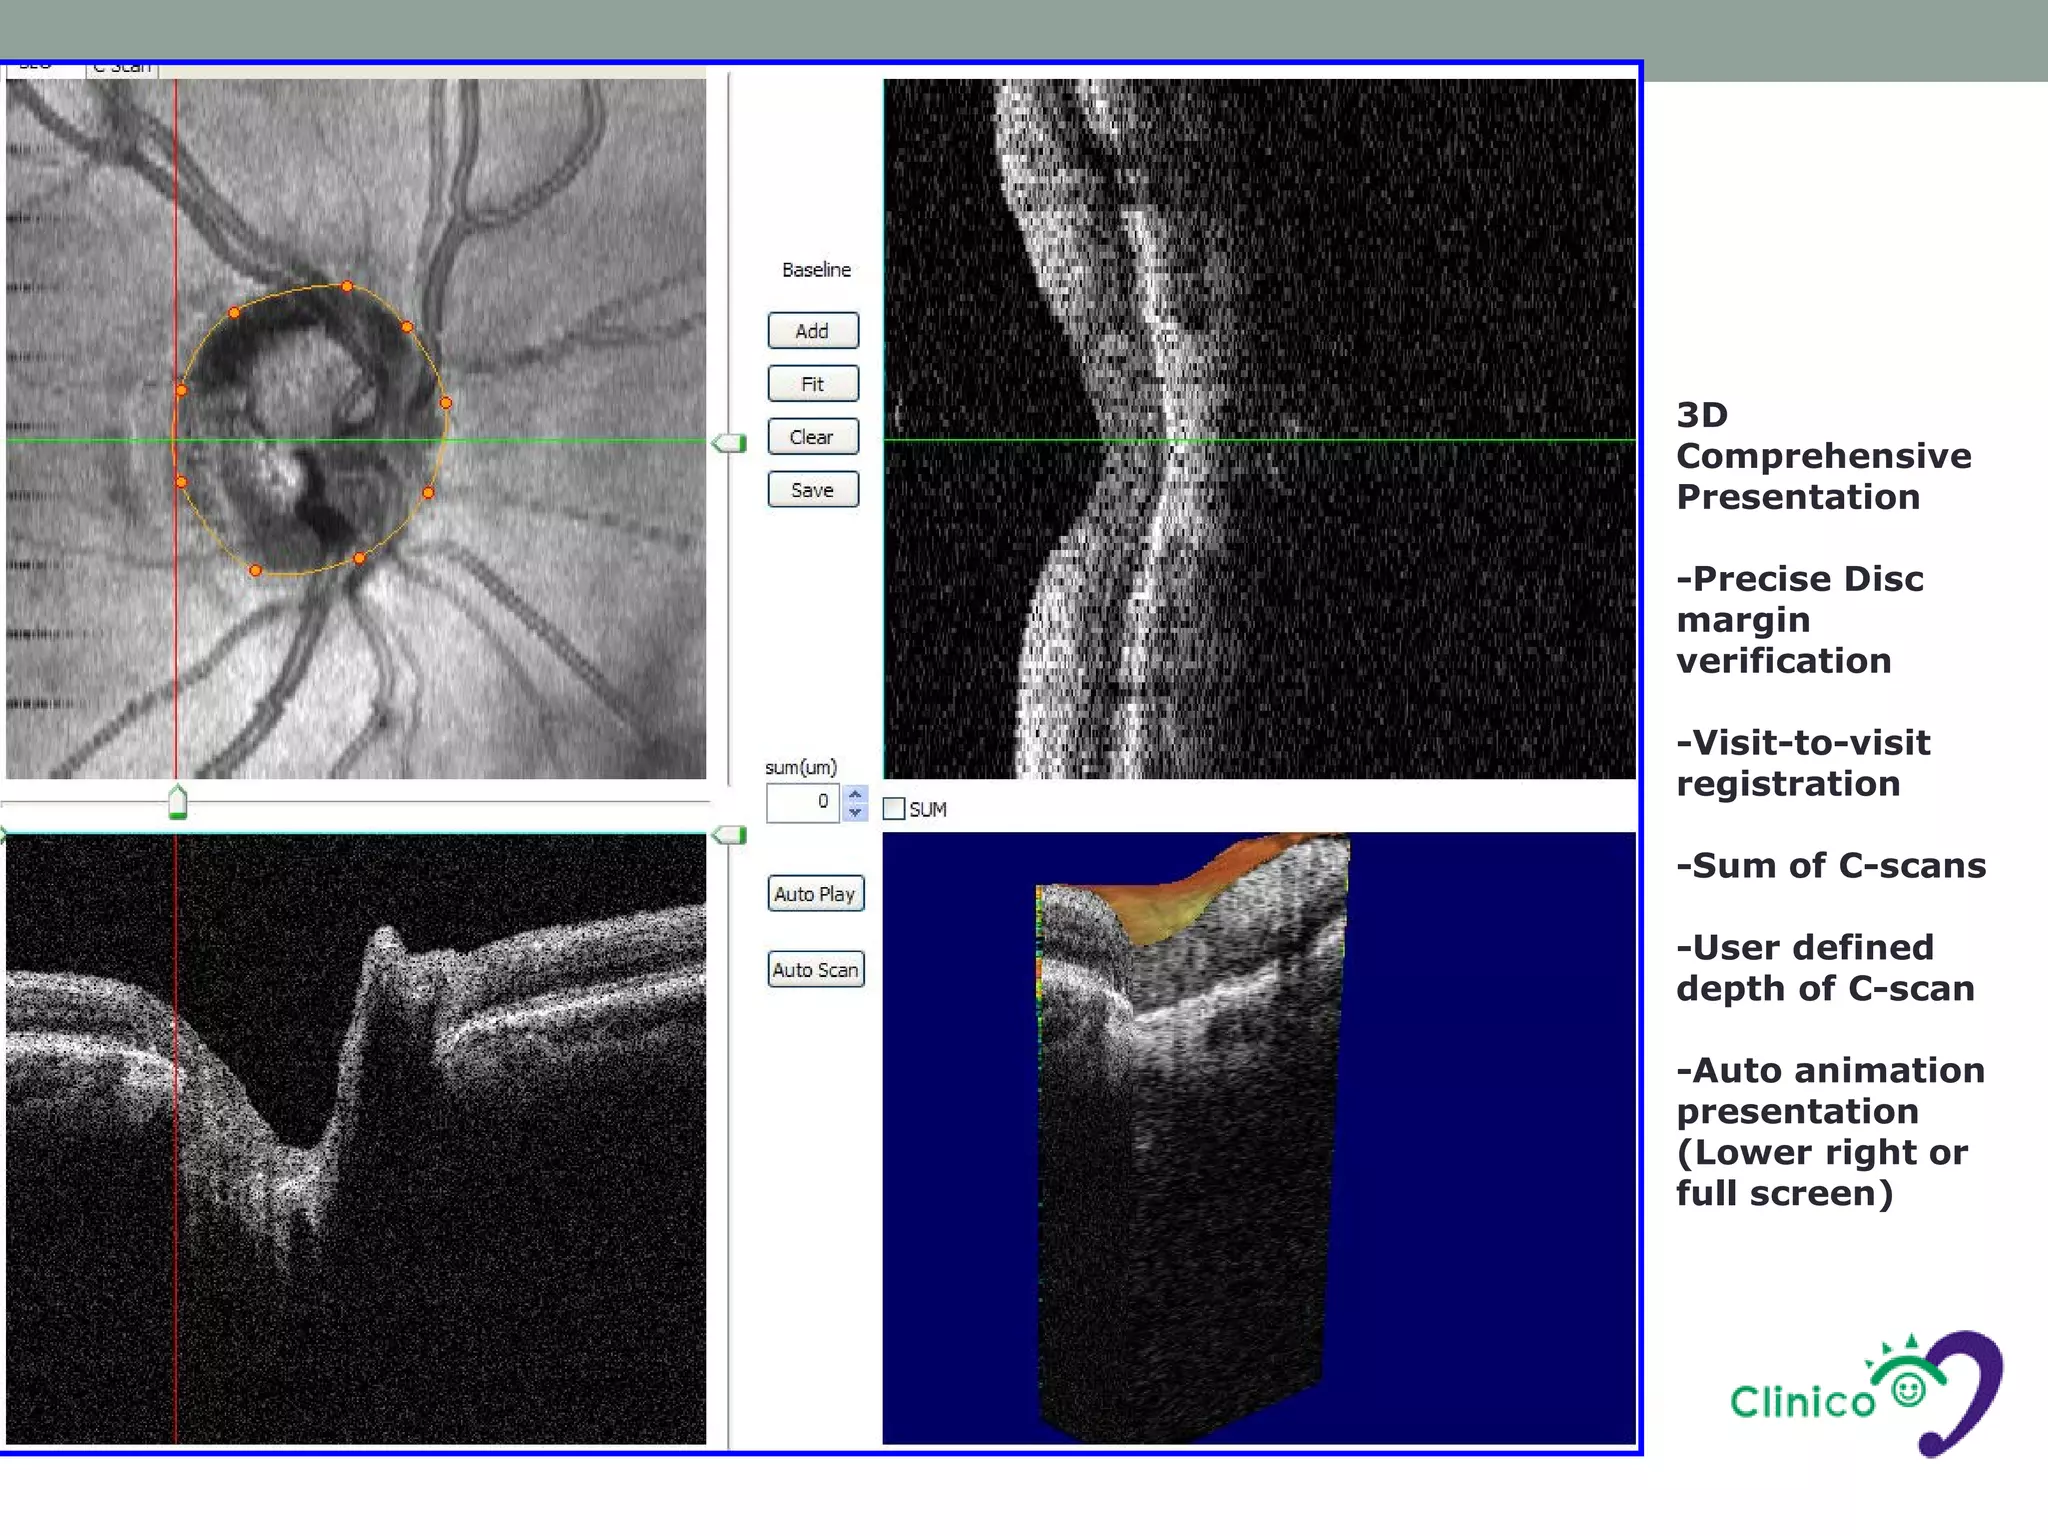

3D

Comprehensive

Presentation

-Precise Disc

margin

verification

-Visit-to-visit

registration

-Sum of C-scans

-User defined

depth of C-scan

-Auto animation

(Lower right or

full screen)

3D Comprehensive Presentation -Precise Disc margin verification -Visit-to-visit registration -Sum ofC-scans -User defined depth of C-scan -Auto animation presentation (Lower right or full screen)

青光眼常用掃描模式 • 3D Discscan • 2.2 seconds 101 frames equally spaced B-scans to cover a square volume • fixation at 20o nasal • 視神經頭3D圖像觀察